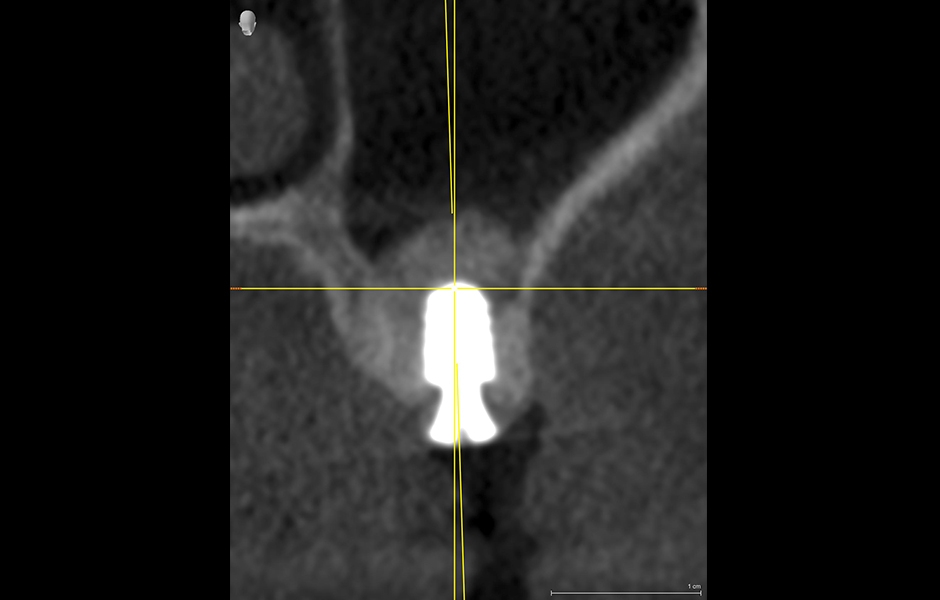

Po 7 měsících potvrdil kontrolní snímek (obr. 9–15) úplné zhojení. Pomocí systému CEREC Primescan IOS jsme začali s plánováním implantace, kdy prvním krokem byl návrh náhrady (obr. 16–18). Po importu dat protetického návrhu do modulu SIDEXIS Sicat Implant Module bylo jasné, že subkrestální umístění implantátu Ankylos B6.6 poskytuje vhodný základ pro plánovanou šroubovanou korunku (obr. 19). Snímek jasně ukázal, že vertikální rozměr kosti v bezpečné zóně je nedostatečný. Chybějící 3 mm však lze nahradit uzavřeným sinus liftem, a to současně se zavedením implantátu. Použití vodicí chirurgické šablony CEREC však není podporováno pro zavádění implantátů B6.6 s naváděcí chirurgickou soupravou. V tomto případě by řešením mohlo být naplánování inzerce 8 mm dlouhého implantátu o průměru 3,5 mm umístěného 1 mm pod kortikální kost v oblasti sinu (obr. 20), které by ve výsledku umožnilo zavedení indikovaného implantátu Ankylos B6.6. Po určení polohy implantátu byl v softwaru CEREC dokončen návrh chirurgické šablony a mohlo být zahájeno frézování na fréze MC XL (obr. 21–22). Chirurgická šablona dokonale definuje polohu implantátu a zajišťuje bezpečné provedení uzavřeného sinus liftu po počátečním vrtání optimální velikostí kostního kondenzátoru Ankylos.

Následně jsme pomocí naváděcí šablony připravili lůžko pro implantát A8: finálního tvaru lůžka jsme dosáhli pomocí kondenzátoru, paralelně se zavedením biomateriálu. Poté jsme manuálně umístili plánovaný implantát B6,6. Po zavedení vhojovacího válečku jsme lalok uzavřeli stehy. Pooperační situaci jsme zhodnotili na bezprostředním snímku (obr. 23–25), který potvrdil, že poloha implantátu i uzavřený sinus lift jsou v souladu s plánem.

Obr. 19

Obr. 20